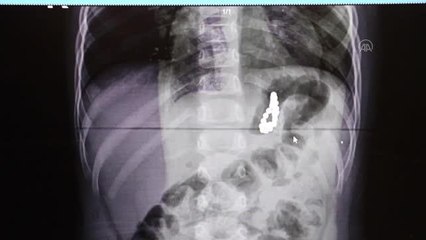

Bursa'da görülmemiş olay! Doktorlar bile şaşırdı: 5 yaşındaki çocuğun bağırsağından 38 adet mıknatıs çıkarıldı